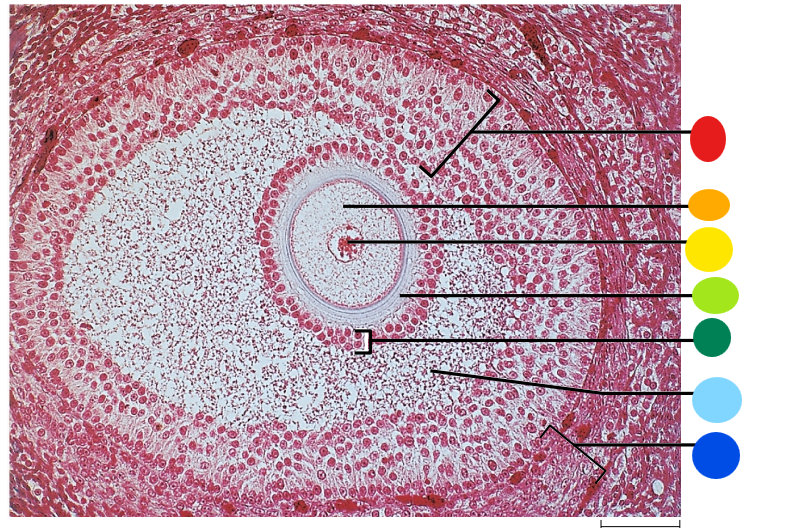

red

tunica albuginea

orange

primordial follicles

yellow

follicular cells

light green

primary oocyte

dark green

granulosa cells

light blue

primary follicles

what is this?

ovary